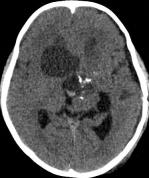

鉴于肿瘤体积超大,而且患儿间断出现意识障碍,直接作手术完全切除肿瘤的难度很大,为降低手术风险,所以我们采用先穿刺肿瘤囊减少肿瘤体积,降低颅压,二期手术争取完全切除肿瘤的策略。行肿瘤囊肿穿刺后,引流出约100多毫升囊液,肿瘤体积显著变小,见图3、图4。

图4.肿瘤囊穿刺手术后肿瘤体积减小

白色箭头示引流管